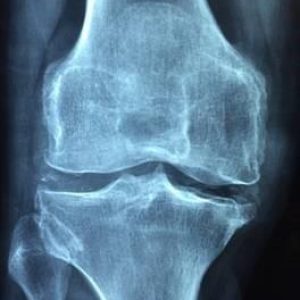

„Treat to Target (T2T)“ – „Rheumatoide Arthritis (RA) – Der Weg zur Beschwerdefreiheit

Was bedeutet Treat to Target? Was hat das mit einer rheumatoiden Arthritis zu tun? Sie kennen dieses Ziel der Beschwerdefreiheit noch nicht? Dieses Ziel sorgt im Idealfall für mehr Lebensqualität bei den Patienten und Patientinnen mit einer rheumatoiden Arthritis.

Im Arzt/Patientengespräch soll ein gemeinsames Behandlungsziel festgelegt werden, um das Stoppen der Erkrankung (Remission) zu erreichen. Die Feststellung der Krankheitsaktivität wird vom Arzt oder Ärztin durch klinische Scores oder Patientenfragebögen erhoben. Sehr wichtig ist, dass die Patienten und die Patientinnen selbst ihre persönlichen Ziele neben der Beschwerdefreiheit im Gespräch dem Arzt oder der Ärztin bekannt geben. Diese gemeinsamen Ziele sollten Schritt für Schritt umgesetzt und Abweichungen auch mit dem Arzt besprochen werden.